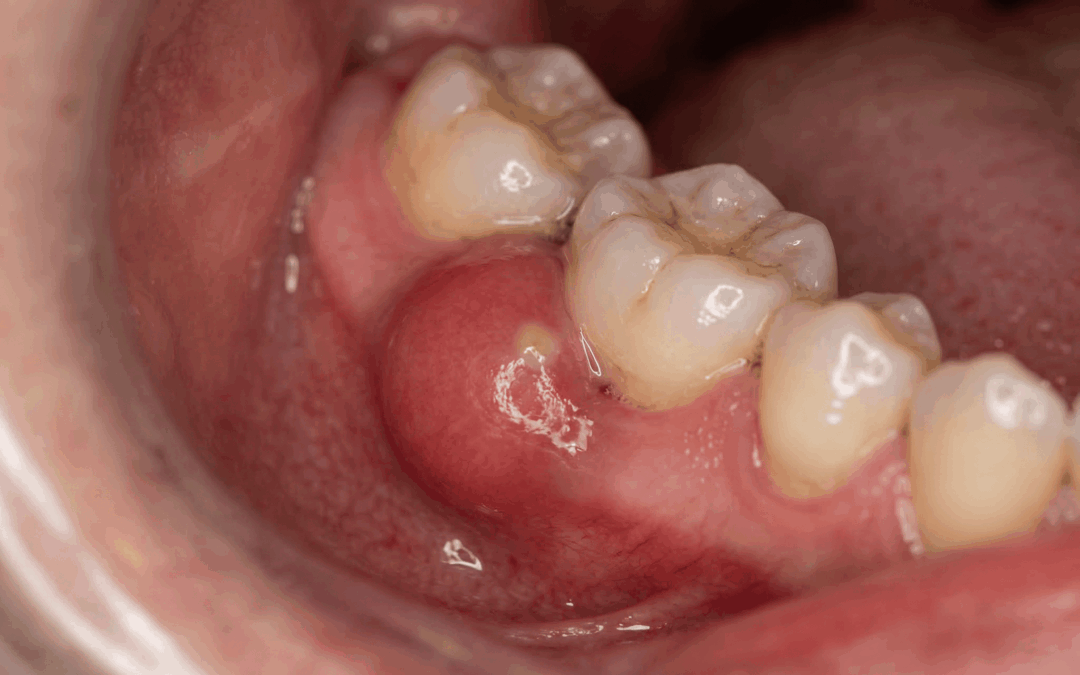

Hay una frase que se repite más de lo que debería: “Me sangran las encías, pero bueno… a mí siempre me ha pasado”. Y claro, si te pasa desde hace tiempo, el cerebro hace lo suyo: lo normaliza. El problema es que la encía sana no sangra. Ni “un poquito”, ni “solo...